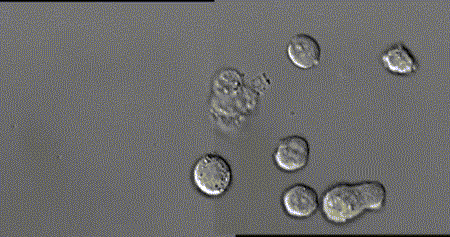

在顯微鏡下“實拍”一場免疫細胞和癌細胞之間的戰(zhàn)爭場面

殺手T細胞正在識別癌細胞并將其殺死

NK細胞成功突破,癌細胞瞬間瓦解